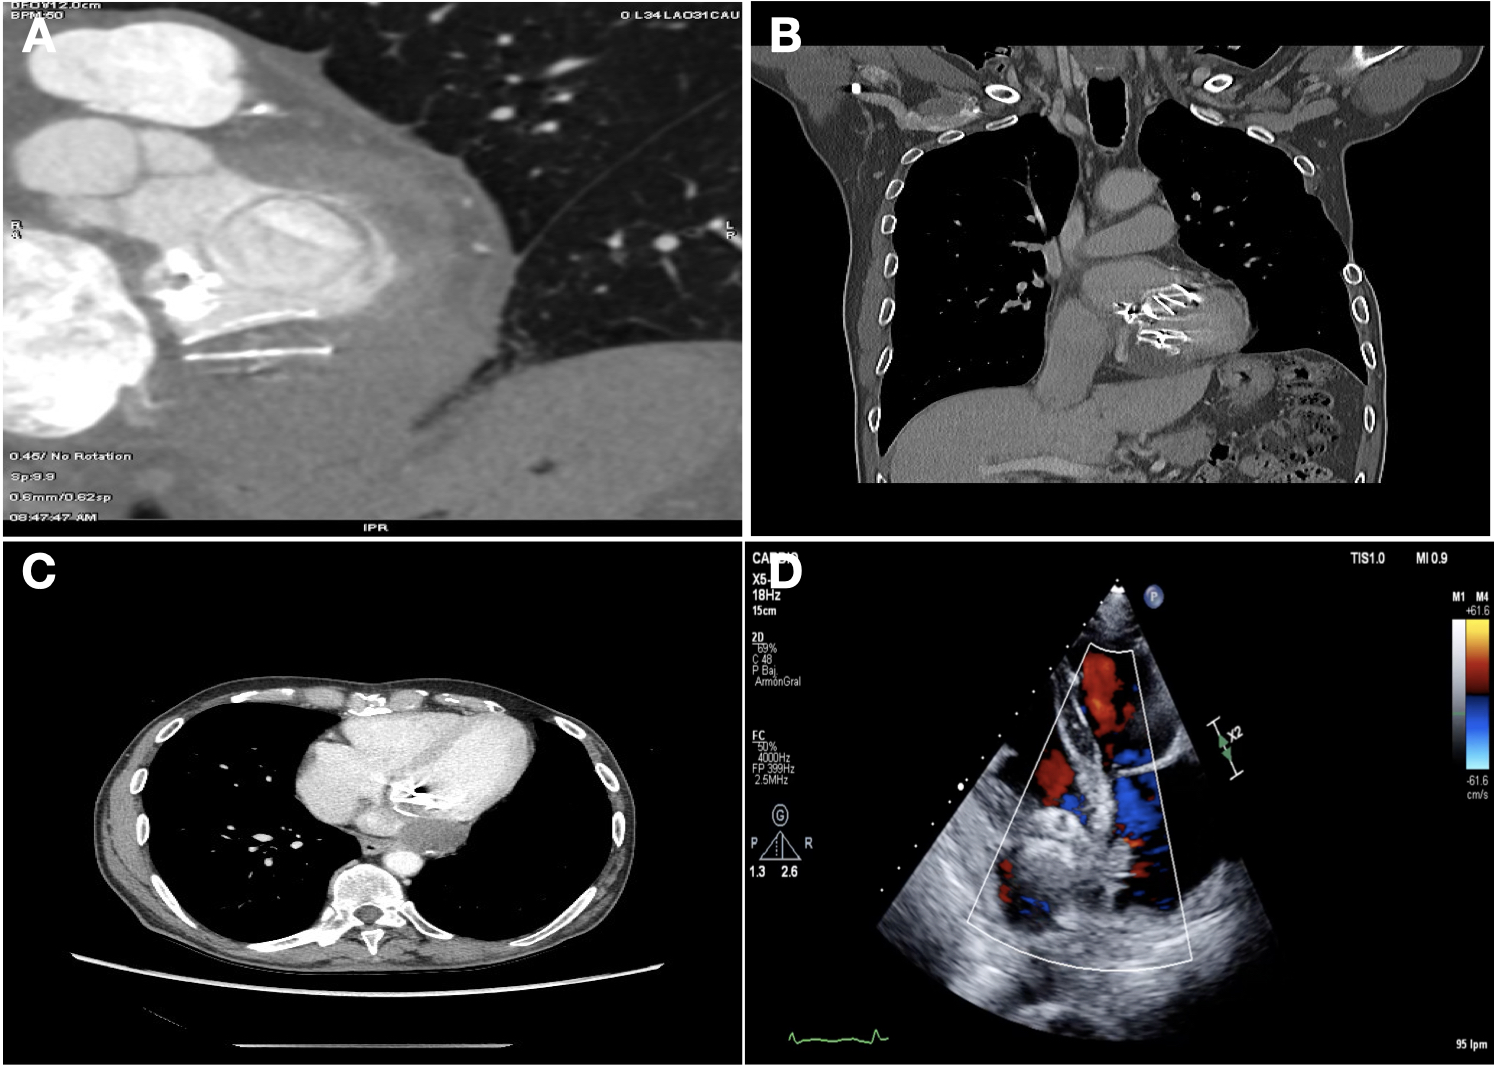

We present a 70-year-old man with rheumatic mitral valve disease who had undergone 3 previous open-heart surgeries, the last of which was a new mitral valve replacement for a mechanical prosthesis due to early bioprosthetic endocarditis. During this intervention, the left atrio-ventricular groove was injured due to tissue frailty, and it was repaired by the surgeon with the patient´s own pleuro-pericardial tissue (Cabrol type repair). The patient was discharged with no clinical complications after 10 days. During the follow-up, a transesophageal echocardiogram (TEE) was performed, which showed both an antero-lateral paravalvular leak and a posterior atrio-ventricular pseudoaneurysm with thrombus burden (Figure 1A and B). The Heart Team discussed the case and, due to surgical risk, decided to perform a single percutaneous procedure to treat both defects.

To complete the examination and for procedure planning, we performed a computed tomography scan, which showed the pseudoaneurysm next to the repaired area with a 15-mm neck that could be accessed percutaneously (Figure 1C-F).